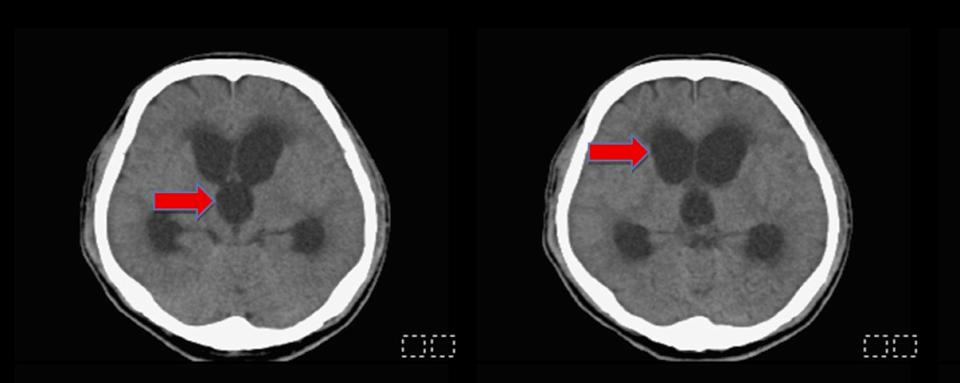

高市48歲男子從事油漆工作過程頭部外傷顱內出血,就醫未開刀治療入住安養機構,突發意識不清及嗜睡送至民生醫院急診,腦部電腦斷層檢查確認水腦症,接受腦室腹腔分流術排出多餘腦脊髓液,術後清醒,恢復正常行動。

神經外科主治醫師陳志豪說,頭傷可能衍生後遺症,其中水腦症肇因腦脊髓液循環不良、吸收異常,導致過量腦脊髓液累積腦部壓迫組織,未即時診療恐造成記憶力下降、步態不穩、意識變差、大小便失禁等症狀,長期損害神經系統。

陳志豪說,臨床可透過電腦斷層(CT)、磁振共振造影(MRI)判斷追蹤評估手術,根據研究適時分流腦脊髓液有助改善神經功能。圖/民生醫院提供、文/高培德